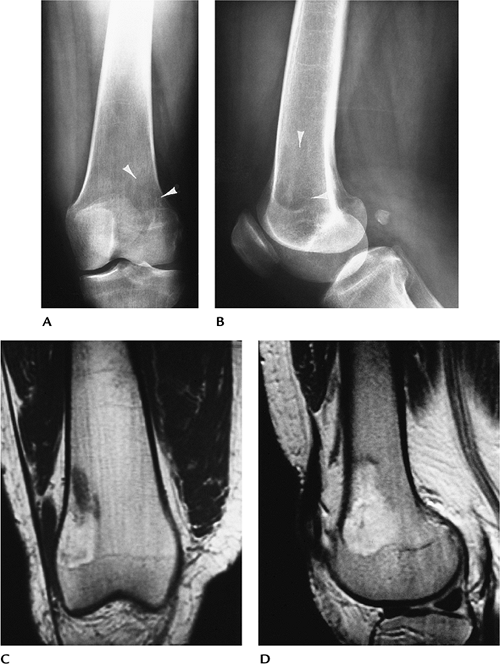

![]() |

FIGURE 12-10 Osseous xanthomas (Type IV hyperlipoproteinemia). (A,B) Routine radiographs showing a poorly defined lytic lesion in the distal femur (arrowheads). Coronal T1-weighted (C) and sagittal T2-weighted (D) MR images showing a poorly defined lesion that has fatty intensity on T1-weighted image (C) and areas of increased intensity on T2-weighted image (D).